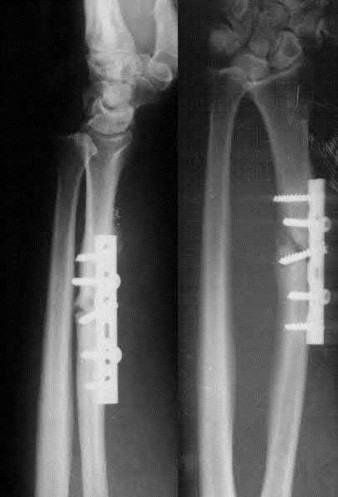

1. # A 32-year-old male sustains the injury shown in Figure A and undergoes treatment as shown in Figure B. Following placement of this implant, what is the best technique to confirm it is not too proud proximally?

The safe zone for tibial nail placement as seen on radiographs is just medial to the lateral tibial spine on the anteroposterior radiograph and immediately adjacent and anterior to the articular surface as visualized on the lateral radiograph.

Tornetta et al specifically located the safe zone for nail entry in a study using fresh frozen cadaver knees. The authors found that the safe zone for nail placement is located 9.1+/-5 millimeters lateral to the midline of the plateau and three millimeters lateral to the center of the tibial tubercle. The width of the safe zone averaged 22.9 millimeters and was as narrow as 12.6 millimeters.

The starting point of the of the nail can be best viewed on the lateral knee radiograph, an example of which is shown in Illustration A. Illustration B shows the "sweet spot" for nail insertion as defined by Tornetta.